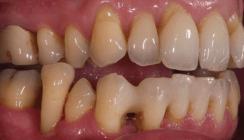

Vor umfangreichen konservierenden und prothetischen Sanierungen sollte eine funktionelle Vorbehandlung erfolgen.

Eine funktionelle Vorbehandlung kann unliebsame Überraschungen bei konservierenden oder prothetischen Versorgungen verhindern. Auch wenn das ästhetische und kariesprotektive Ergebnis zunächst ein dauerhaft gesund funktionierendes Kauorgan suggerieren mag, können die zahn- und zahnersatzbezogenen Voraussetzungen einer funktionellen Diskoordination (unbeabsichtigt) „eingebaut“ werden. So geschehen bei dem nachfolgend geschilderten Patientenfall.

Diese heute 45-jährige Patientin wurde vor ca. 19 Jahren in allen vier Quadranten vom Autor dieses Artikels mit Goldinlays und -overlays versorgt, war und ist regelmässig in erwachsenenprophylaktischer Betreuung und hat eine gute Mundhygiene. Lediglich im Jahr 2006 war nochmals die Anfertigung und Eingliederung eines keramischen Inlays an Zahn 14 notwendig gewesen.

Ende 2014 berichtete sie, dass sie seit mehreren Monaten von verschiedenen medizinischen Fachkollegen (Orthopäde, Physiotherapeut, Psychologe) wegen unterschiedlicher Beschwerden resp. Schmerzen behandelt worden sei. In der subjektiven Vorbefundung klagte sie z. B. über Spannungskopfschmerz, Nacken-, Kiefer-, Ohren- und Schulterschmerzen, Schwindel, gab aber auch an, mit den Zähnen zu pressen, dass diese nicht richtig aufeinander passen, sie nur auf einer Seite kaute und sie verschiedene Positionen mit ihren Zähnen einnehmen könne. Weder die Kollegen noch die Patientin dachten an die Möglichkeit, das stomatognathe System mit zu untersuchen. Auch von zahnmedizinischer (unserer) Seite wurde bis dahin nichts unternommen, da die Patientin stets mit einer gewissen Gelassenheit unsere Sprechstunde zum Recall aufsuchte und deshalb kein Anlass zu anderen Untersuchungen (auch wenn, wie später zu berichten sein wird, objektive Hinweise vorhanden waren) bestand.